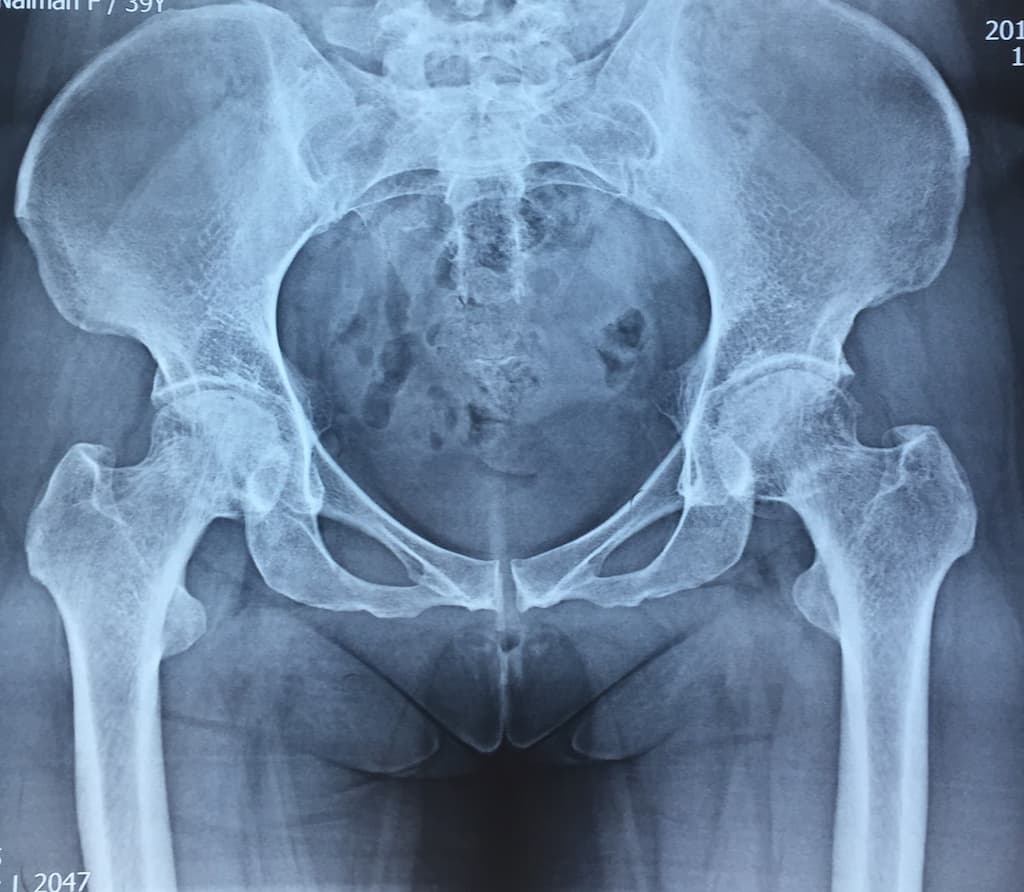

Түнхний үе солих мэс засал гэж юу вэ image1Түнхний үе солих мэс засал гэж юу вэ image2

Остеоартрит

Остеоартрит нь ихэвчлэн 50 болон түүнээс дээш насныханд үений мөгөөрсөн эдийн тэжээл, уян чанар , алдагдсанаар үүсдэг өвчин юм. Мөгөөрсөн эдийн гөлгөр гулсамтгай шинж чанар алдагдаж, өвчин даамжирсаар үе хоорондын мөгөөрсөн эдийн бүтэц алдагдан үгүй болж , үе үүсгэж буй яснууд хоорондоо үрэлцэх энэ тохиолдолд хүчтэй өвдөлт үүсдэг. Зарим судлаачид энэхүү өвчнийг удамшилтай холбоотой ч гэж үздэг. Мөн биеийн жингийн илүүдэл, гэмтэл бэртэл, төрөлхийн үений эмгэг, тэнхлэгийн гажиг нь остеоартрит өвчин үүсэхэд нөлөөлдөг.